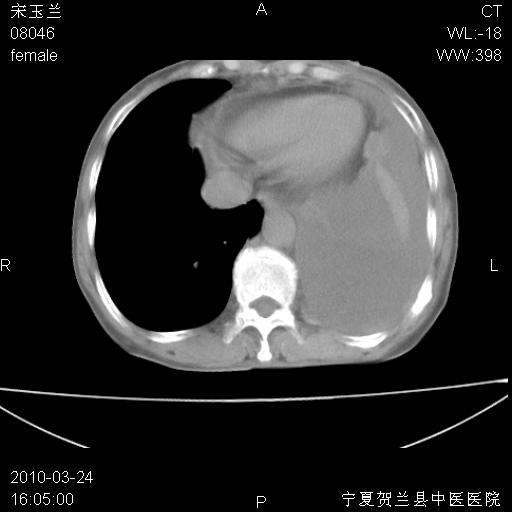

以下是引用随光逐影在2010-3-24 19:15:00的发言:[br]结合病史,考虑双肺及纵隔淋巴结多发转移、左侧胸膜转移并左侧大量胸水,左下肺膨胀不全。

以下是引用zxl51642在2010-3-24 18:49:00的发言:[br]结合乳腺癌术后病史,考虑双肺及纵隔淋巴结多发转移、左侧胸膜转移并左侧大量胸水、左下肺膨胀不全。